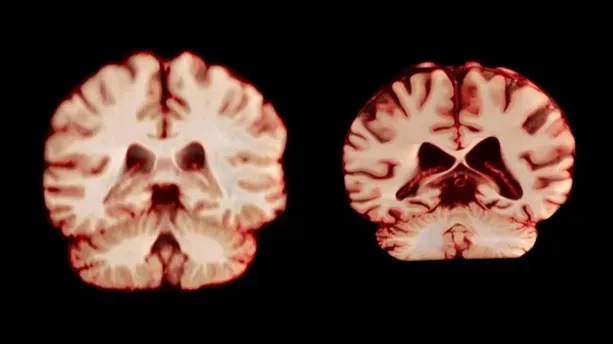

Параллельно нейробиологи из Университета Осло проанализировали 12 500 МРТ-сканов и обнаружили, что у мужчин мозг с возрастом уменьшается быстрее и в большем числе областей, чем у женщин. Правда, это не объясняет, почему женщины чаще страдают болезнью Альцгеймера.

«Если бы женский мозг старел быстрее, женщины демонстрировали бы большее уменьшение гиппокампа», — поясняет соавтор исследования Анне Равндаль. Ученые предполагают, что разница в распространенности болезни связана не со скоростью старения мозга, а с генетикой и социальными факторами, включая уровень образования и стресс.

Anatomical Travelogue/SPL